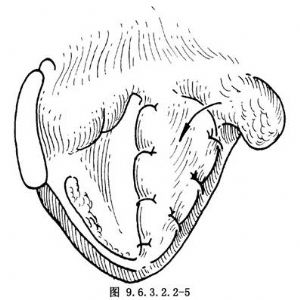

將預先形成的患側軟骨瓣(患側橫徑全長,寬0.5cm的軟骨條),翻入聲帶已切除側喉腔,用0號細絲線縫合固定,前方固定在環狀軟骨上,後方固定在後板上分離梨狀窩黏膜,遮蓋在軟骨瓣上間斷縫合(圖9.6.3.2.2-4)。此時改爲淺麻醉,用吸引管頭刺激喉氣管黏膜,觀察健側聲帶活動時是否達到聲門閉合。如聲門裂大,可取帶狀肌遊離肌瓣植入軟骨瓣上的梨狀窩黏膜下,再重新縫合梨狀窩黏膜(圖9.6.3.2.2-5)。